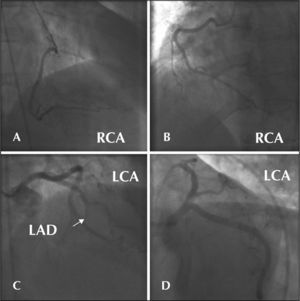

The major limitations to using gadolinium in angiography are the opacity, which is less than that of the iodinated contrast, and the maximum volume that can be used. In these cases, the images were of acceptable quality, clearly defining the coronary anatomy and the presence or absence of obstructive lesions (Figures 1 and 2).

– Case 1. A) Right coronary artery in the right anterior oblique view. B) Right coronary artery in the left anterior oblique view. C) Left coronary artery in the right anterior oblique cranial view and the left anterior descending artery with total obstruction in the middle third (arrow). D) Left coronary artery in the left anterior caudal oblique view. RCA = right coronary artery, LCA = left coronary artery, LAD = left anterior descending artery.